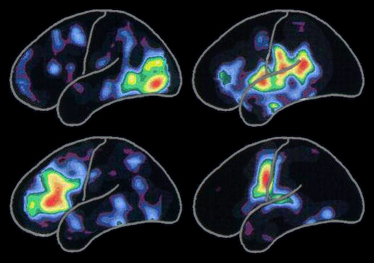

Tomografski snimak emitovanja pozitrona (PET na engleskom) na lijevoj strani pokazuje tipične uzorke aktivnosti mozga asociranih sa:

Aktivnost je največa u crvenim oblastima i onda se smanjuje kroz druge dugine boje od žute do plavo-ljubičaste.

Specifični  uzorci aktivnosti se mijenjaju tokom života kako upoznajemo nove ljude, stićemo nova iskustva i nove sposobnosti. Uzorci se takođe mijenjaju kada Alzheimer bolest, ili sa njom povezani poremećaji,  prekinu nervne ćelije i njihove međusobne veze.